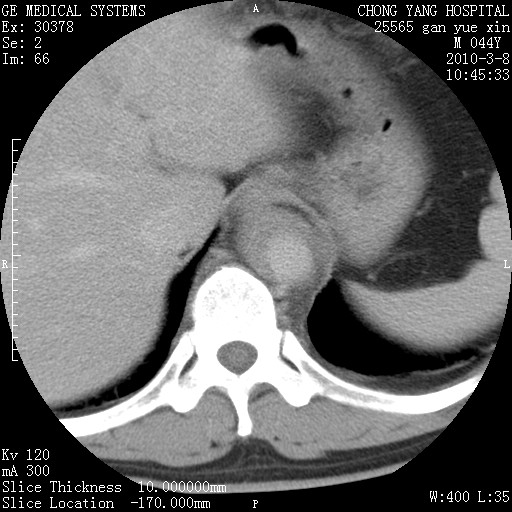

标题: CT24940:主动脉增强,典型病例。 [打印本页]

标题: CT24940:主动脉增强,典型病例。

夹层动脉瘤。

动脉夹层

夹层动脉瘤,典型

主动脉夹层。

动脉夹层的分型:

⒈debakey分型:根据主动脉夹层累及部位,分为三型:ⅰ型:原发破口位于升主动脉或主动脉弓部,夹层累及升主动脉、主动脉弓部、胸主动脉、腹主动脉大部或全部,少数可累及髂动脉。ⅱ型:原发破口位于升主动脉,夹层累及升主动脉,少数可累及部分主动脉弓。ⅲ型:原发破口位于左锁骨下动脉开口远端,根据夹层累及范围又分为ⅲa,ⅲb。ⅲa型:夹层累及胸主动脉。ⅲb型:夹层累及升主动脉、腹主动脉大部或全部。少数可累及髂动脉。

⒉stanford分型:a型:夹层累及升主动脉,无论远端范围如何。b型:夹层累及左锁骨下动脉开口以远的降主动脉。

夹层动脉瘤,少量胸水

夹层动脉瘤;左侧少量胸腔积液。

典型主动脉夹层。